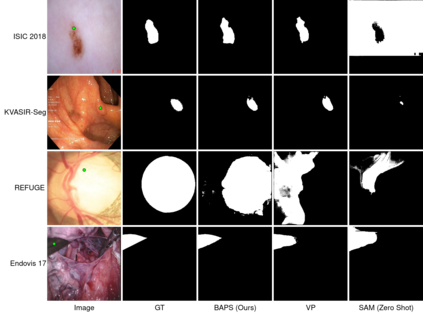

In recent years, various large foundation models have been proposed for image segmentation. There models are often trained on large amounts of data corresponding to general computer vision tasks. Hence, these models do not perform well on medical data. There have been some attempts in the literature to perform parameter-efficient finetuning of such foundation models for medical image segmentation. However, these approaches assume that all the parameters of the model are available for adaptation. But, in many cases, these models are released as APIs or blackboxes, with no or limited access to the model parameters and data. In addition, finetuning methods also require a significant amount of compute, which may not be available for the downstream task. At the same time, medical data can't be shared with third-party agents for finetuning due to privacy reasons. To tackle these challenges, we pioneer a blackbox adaptation technique for prompted medical image segmentation, called BAPS. BAPS has two components - (i) An Image-Prompt decoder (IP decoder) module that generates visual prompts given an image and a prompt, and (ii) A Zero Order Optimization (ZOO) Method, called SPSA-GC that is used to update the IP decoder without the need for backpropagating through the foundation model. Thus, our method does not require any knowledge about the foundation model's weights or gradients. We test BAPS on four different modalities and show that our method can improve the original model's performance by around 4%.